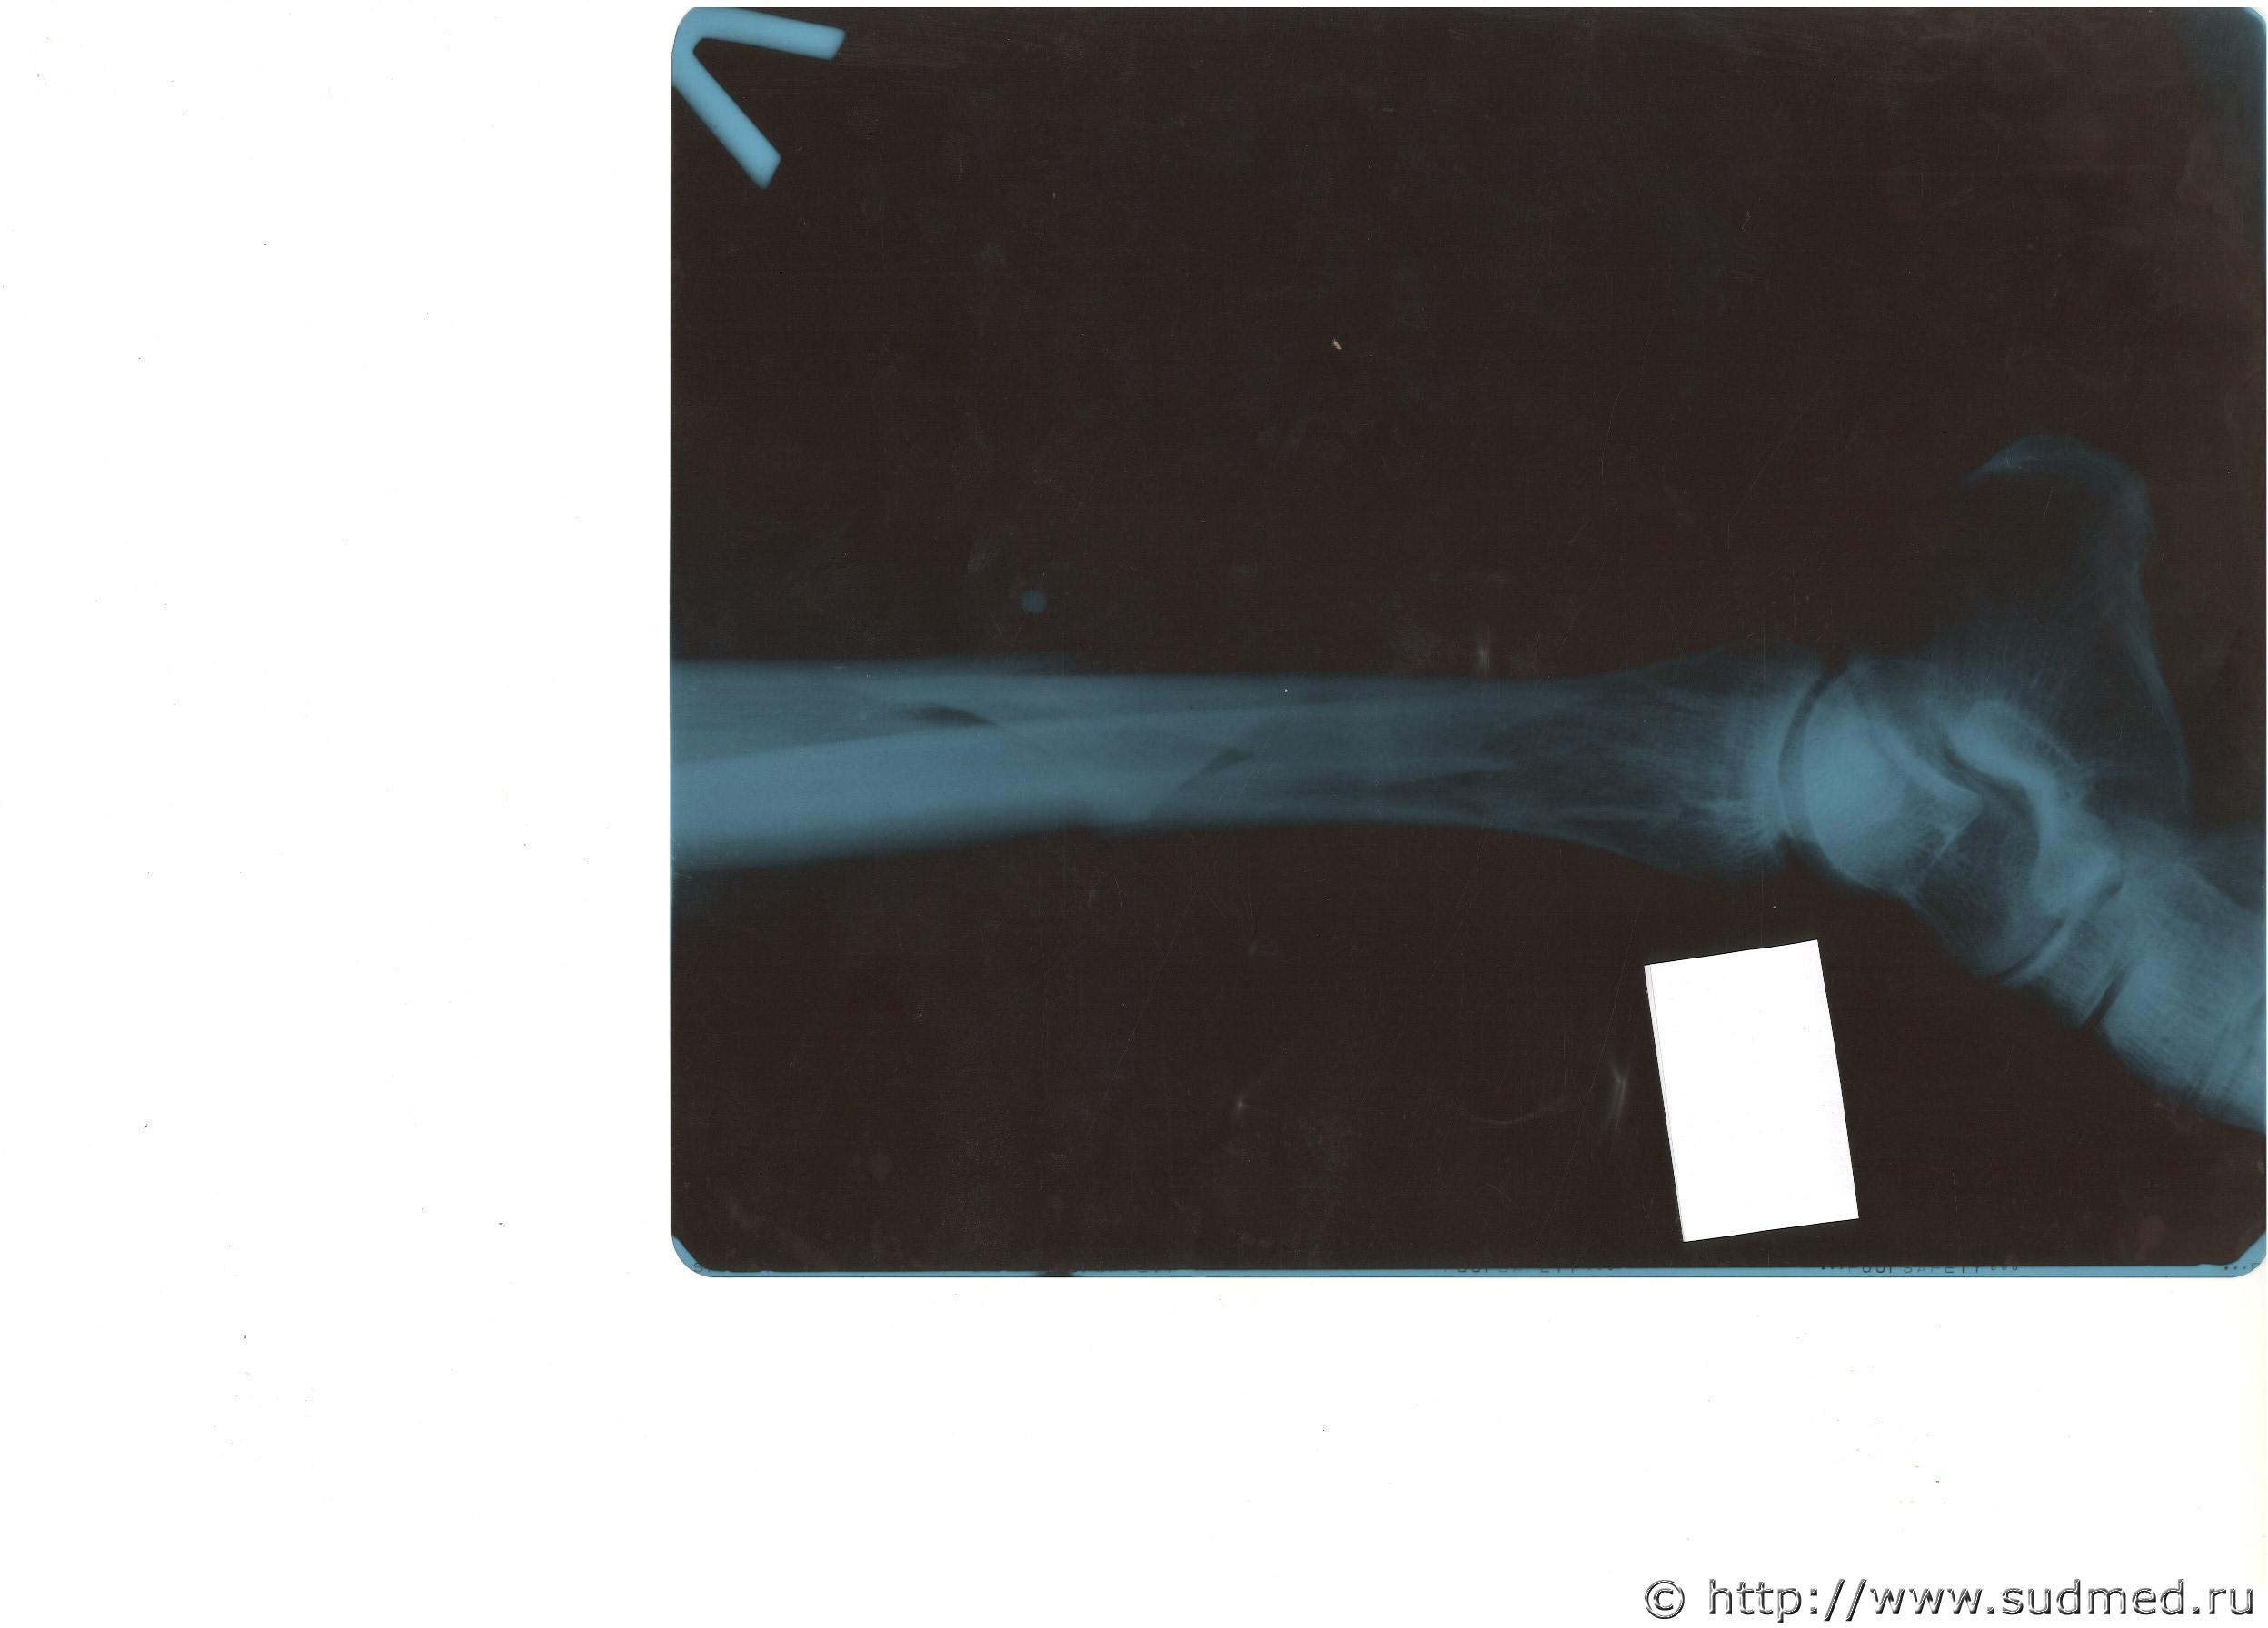

Здесь снимки до оказания медицинской помощи.

Судебная медицина - Прикрепленное изображение Судебная медицина - Прикрепленное изображение

Интересный перелом.

1. Это винтообразный перелом, который обычно образуется в результате ротации (вращения) тела с опорой на одну ногу ( одна из костей этой ноги и ломается).

2. Образование такого перелома в результате удара исключается.

Перелома малоберцовой (второй) кости не вижу.

Винтообразный перелом диагностируется прежде всего по характеру линии перелома.

Образуется он в результате вращательного движения туловища. Какого-либо дополнительного удара для его образования не требуется.

Прыгая на голени большеберцовую кость вообще нельзя сломать.

Будьте добры, посмотрите еще один снимок. Дабы развеять сомнения. Сделан сразу после оказания первой помощи в больнице.

Судебная медицина - Прикрепленное изображение

Здесь в верхнем левом углу снимка, ниже перелома основного, ближе к ступне, в месте крепления аппарата, между двумя шпильками - это не перелом? (снимок размещен в перевернутом положении).

Этот снимок Ваше мнение не меняет по основному вопросу?